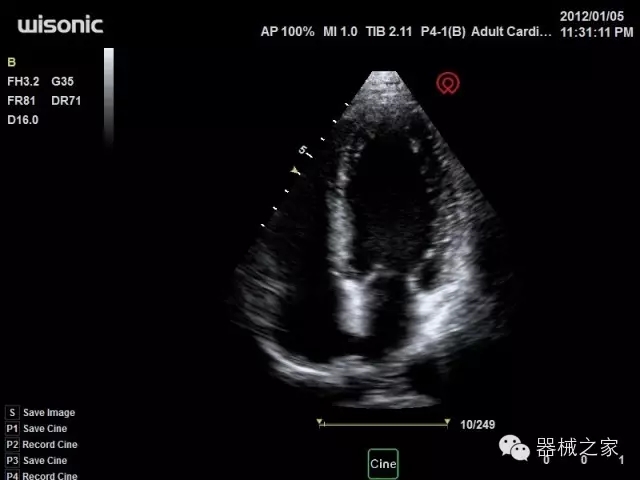

臨床圖片賞析

·全球目前唯一一款配備主機(jī)雙探頭接口,整機(jī)重量(含電池)在5公斤以內(nèi)的便攜式彩超;

·移植S40高端臺式彩超高端平臺技術(shù),滿足超聲科腹部、淺表、婦產(chǎn)科、心血管、肌骨等應(yīng)用,提供超聲科完美解決方案;